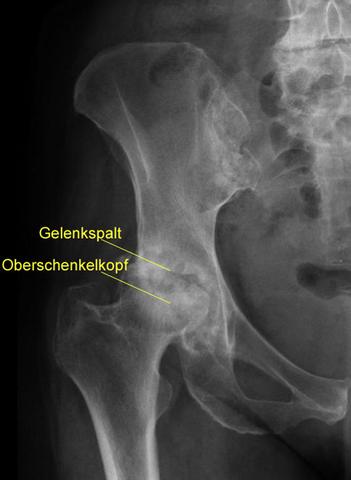

Bei einer Hüftoperation wird in den meisten Fällen eine Totalendoprothese (TEP) verwendet, bei der sowohl die Gelenkpfanne als auch der Gelenkkopf ausgetauscht werden. Die Methode kann entweder zementfrei oder zementiert sein. Beide Methoden haben ihre Vor- und Nachteile, wobei die Entscheidung von Faktoren wie dem Alter des Patienten und eventuellen Risikofaktoren abhängt.